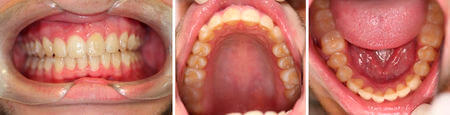

BEFORE

AFTER

Invisalign to correct deep bite and uneven smile, no teeth were removed.